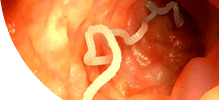

ГЕЛЬМИНТЫ ПОРАЖАЮТ ИЗНУТРИ, РАЗМНОЖАЮТСЯ И ВЫЗЫВАЮТ СМЕРТЕЛЬНЫЕ ЗАБОЛЕВАНИЯ!

Самки паразитов откладывают до 240 000 яиц в кишечнике человека ежедневно.

Размеры гельминтов (глистов) колеблются от нескольких сантиметров до 7-10 метров.